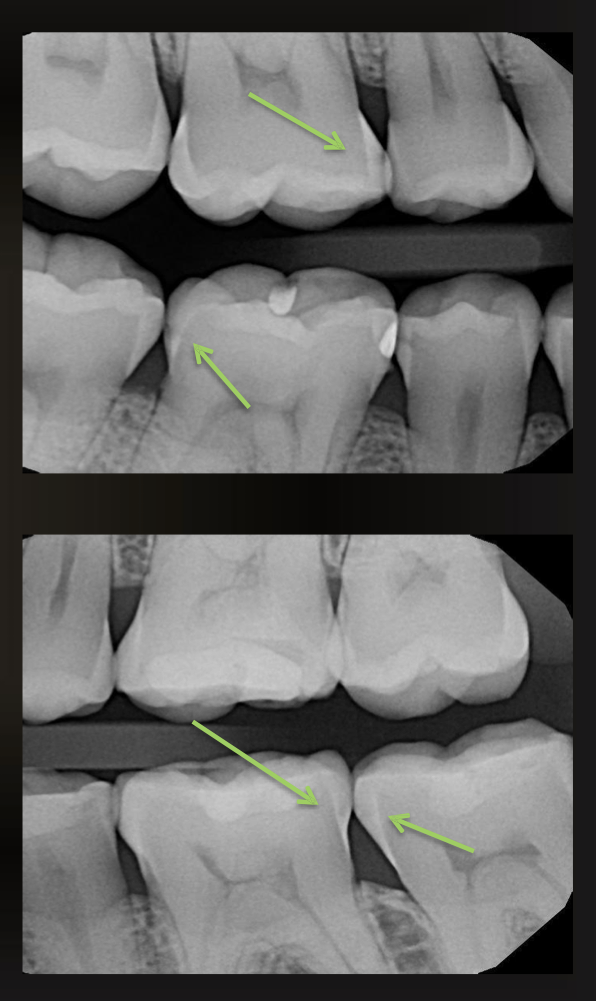

what are the arrows pointing to?

incipient interproximal caries

what do these images have?

interproximal caries (not incipient)

are these caries or restorations with radiolucent material?

caries

are these caries or restorations with radiolucent materials?

restorations with radiolucent materials

what is this arrow pointing at?

secondary caries